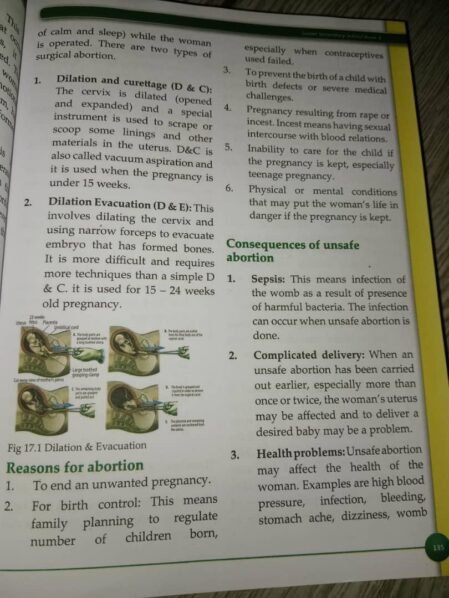

Page 135 of the book partly reads, “There are two types of surgical abortion. Dilation and curettage (D & C): The cervix is dilated (opened and expanded) and a special instrument is used to scrape or scoop some linings and other materials in the uterus. D&C, also called vacuum aspiration, is used when the pregnancy is under 15 weeks.

“Dilation Evacuation (D & E): This involves dilating the cervix and using narrow forceps to evacuate the embryo that has formed bones. It is more difficult and requires more techniques than a simple D & C. It is used for 15-24 weeks old pregnancy.”